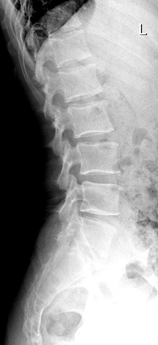

主诉:腰部疼痛1年余,伴左下肢疼痛麻木3月。 病史:女性患者,53岁。患者1年余前在做家务时出现腰部剧烈疼痛,当时腰部活动受限,在外院门诊诊断为腰肌劳损,给予对症治疗,效果较好。1年余来活动后腰部均出现疼痛,反复出现。最近3年以来,患者腰部疼痛时间延长,加重,并伴左下肢麻木,放射痛至足踝处。患者一般情况尚可。

查体:腰4/5、腰5/骶1棘间及左右棘旁轻压痛、叩击痛,左侧坐骨神经出口处明显压痛。左小腿外侧感觉略减退,左侧伸膝、踇背伸肌力4级,左侧直腿抬高试验20°(+),加强(+),Lasegue征(+),左侧4字征(+),左侧股神经牵拉试验(+)。双侧Babinski 征及Oppenheim 征(-)。 辅助检查:三大常规、血生化、肝肾功能均未见明显异常。患者腰椎动力位片正常,其余重要腰椎影像学如下。

诊断:腰椎间盘突出症(L4/5) 治疗:患者入院后尽快完善相关检查,患者目前腰椎稳定性尚可,暂拟”椎间孔镜微创“治疗。